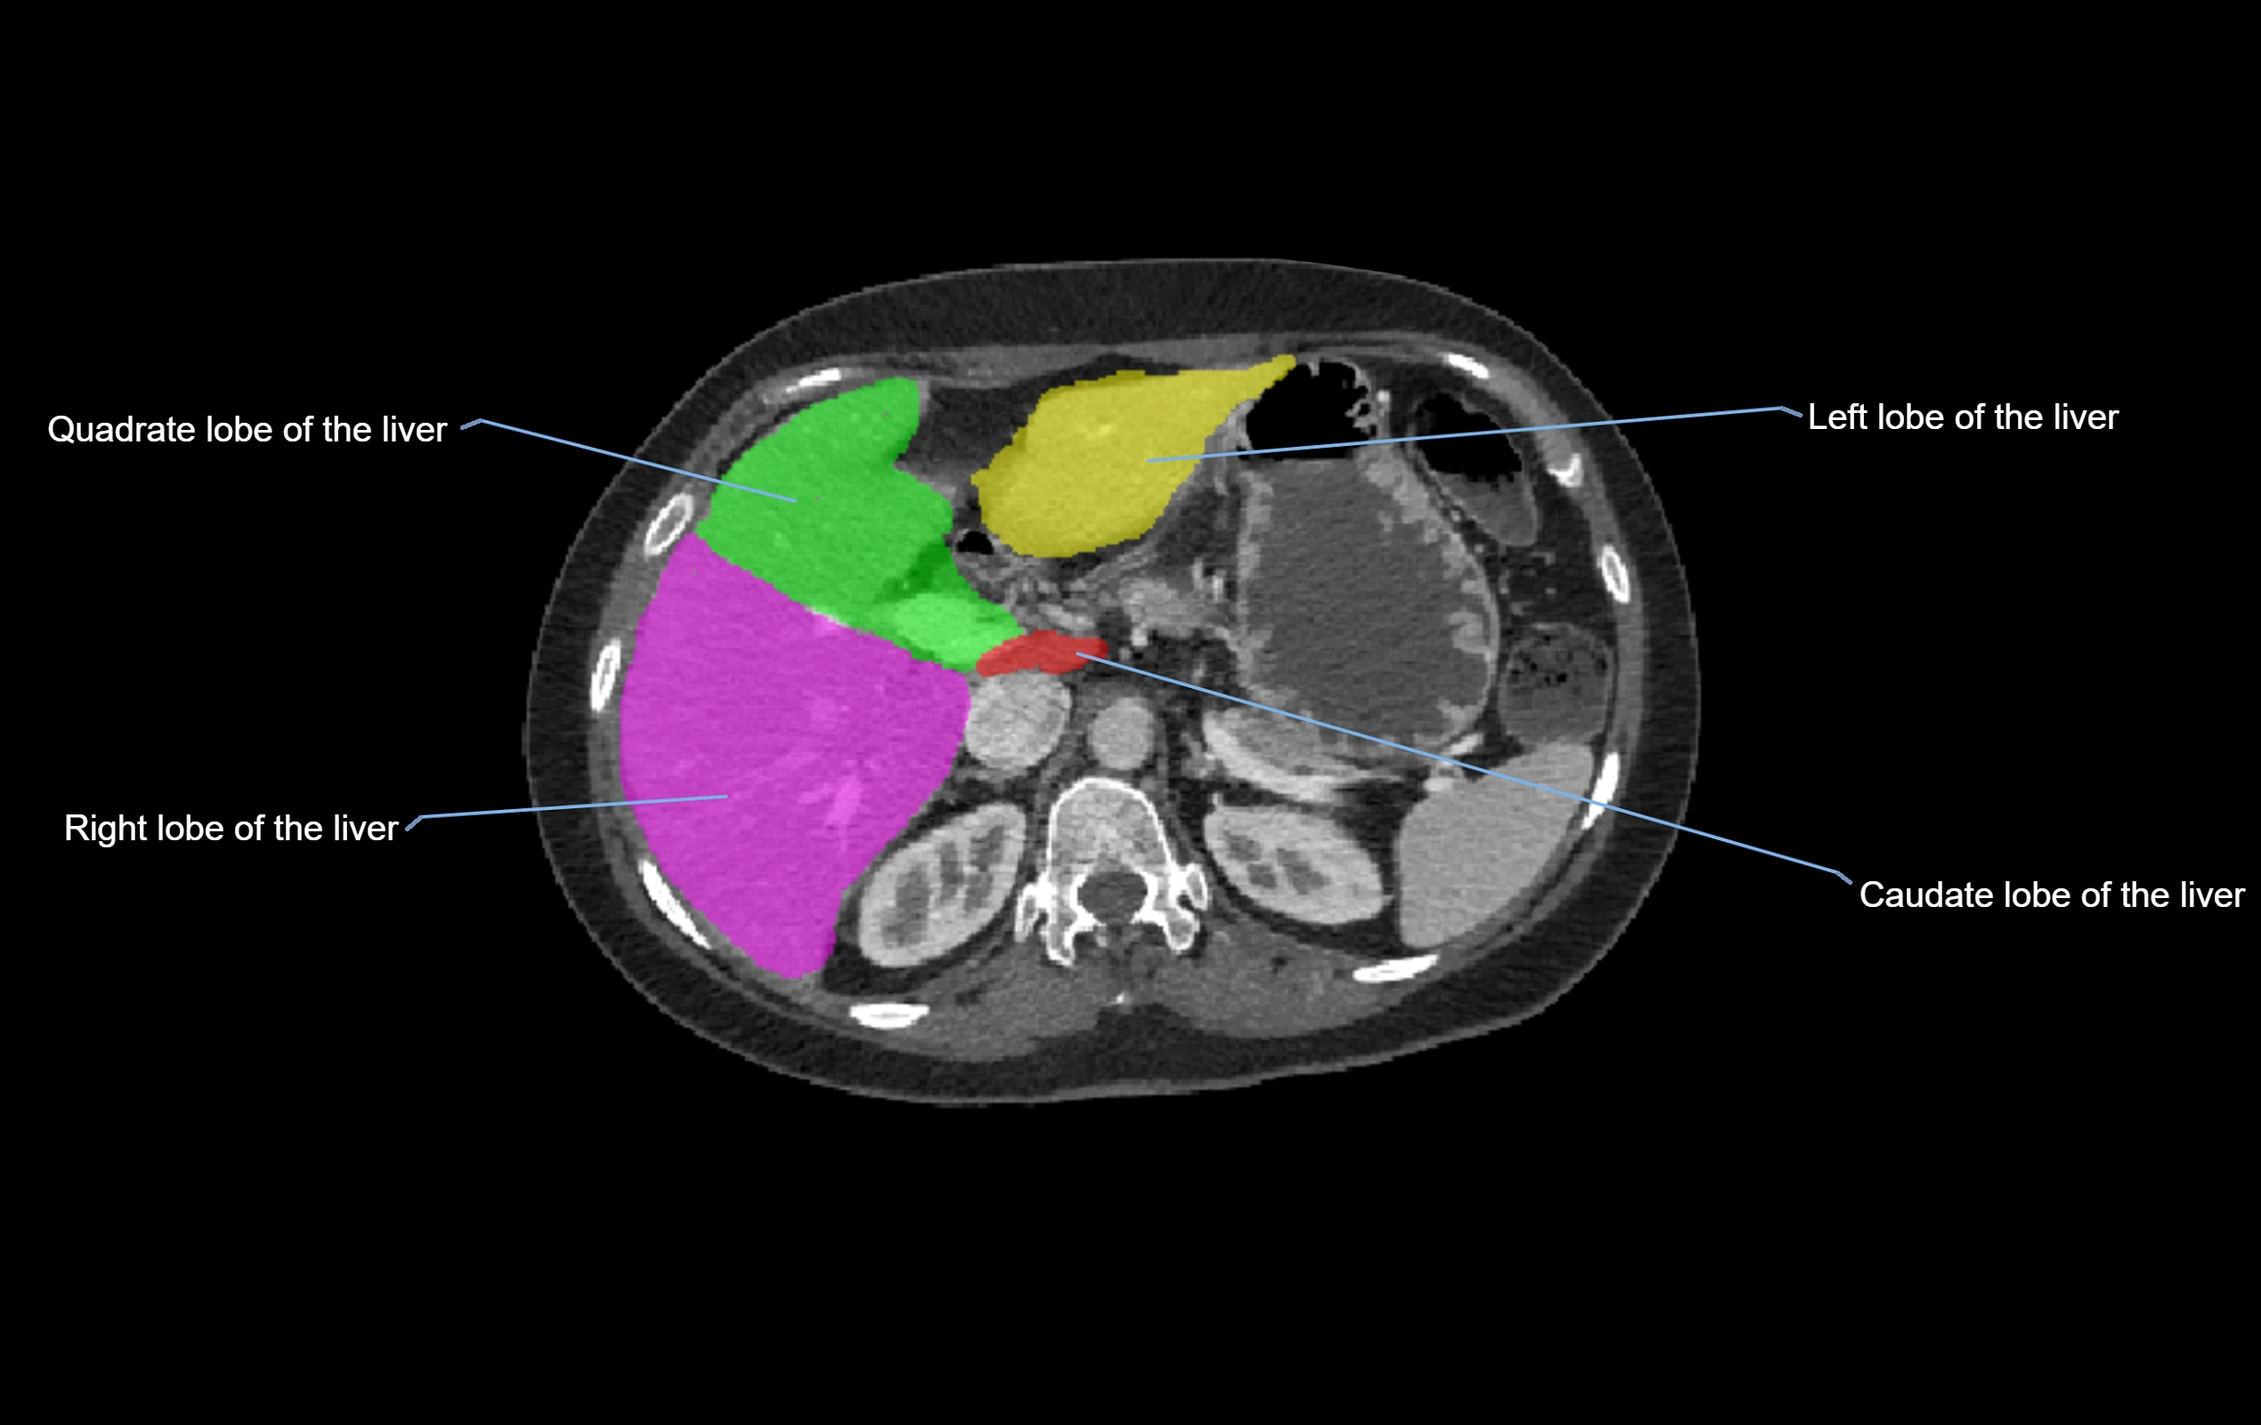

The caudate lobe of the liver is a distinct anatomical subdivision of the liver, designated as segment I in Couinaud’s classification. It lies on the posterior surface of the liver, between the fissure for the ligamentum venosum (left boundary) and the groove for the inferior vena cava (IVC) (right boundary). Superiorly, it is related to the posterior liver surface, and inferiorly it is separated from the left lobe by the porta hepatis.

The caudate lobe is unique because it receives dual portal venous and arterial inflow from both the right and left portal veins and hepatic arteries. It also has independent venous drainage directly into the IVC via multiple small hepatic veins, unlike other lobes that drain through the three main hepatic veins.

MRI image

image